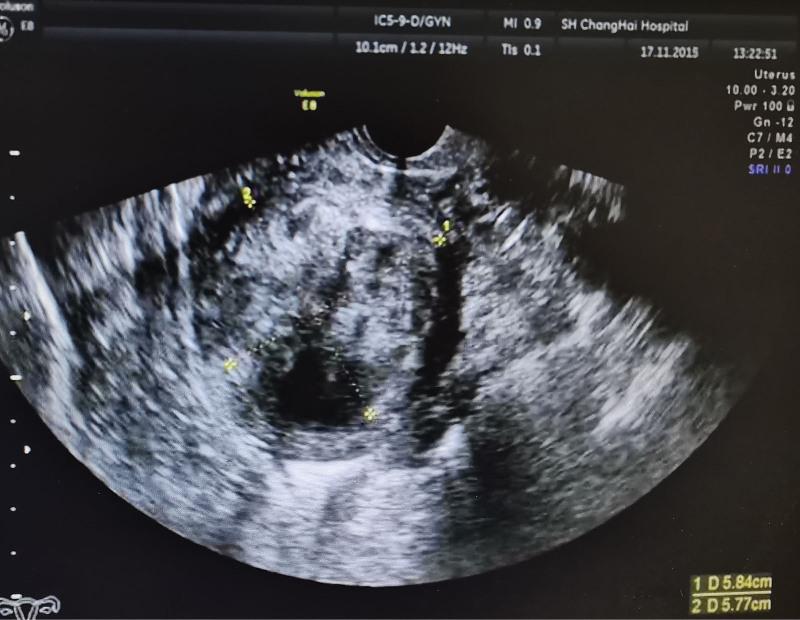

The patient was diagnosed with uterine leiomyoma.

The patient refused the suggestion of surgery, she was continuously treated with an ultra-low-dose (12.5 mg per 5 days) of mifepristone monotherapy for 4 years.

The uterine leiomyoma was stable, anemia and other symptoms disappeared, and the menstrual cycle, liver and kidney function, and tumor markers were normal.